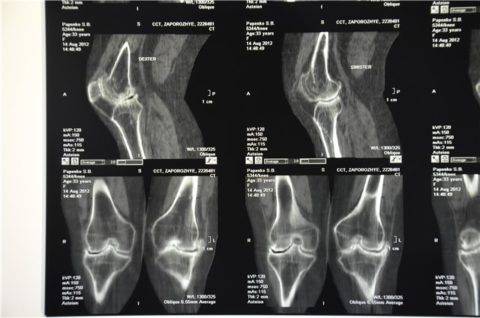

- КТ/МРТ – для послойного динамического обследования.

Для более подробного изучения ситуации рекомендуется пройти МРТ, хоть ценаможет отпугнуть некоторых пациентов. Тем не менее, этот метод считается наиболее информативным, так как демонстрирует состояние мягких и костных тканей в разрезе в разных проекциях.

Клиническая картина артроза, особенно осложненного синовитом, довольно схожа с симптоматикой многих воспалительных патологий опорно-двигательного аппарата. Поэтому проводится дифференциальная диагностика для исключения артритов, тендинитов, тендовагинитов. С помощью инструментальных исследований определяется состояние коленного сочленения и степень его функциональной активности. В диагностике артроза наиболее информативна рентгенография. На полученных изображениях хорошо заметны сформировавшиеся остеофиты, суженная суставная щель, деформация костных структур (кисты, субхондральный остеосклероз).

Симметричное сужение суставной щели коленных суставов, пораженных артрозом. Вероятно, подвергать операции придется обе конечности.

Более детально оценить изменения в гиалиновом хряще позволяют УЗИ, МРТ, КТ. Исследования также проводятся для выявления воспалительного или дегенеративного поражения мягких тканей, мышц, связок и сухожилий.